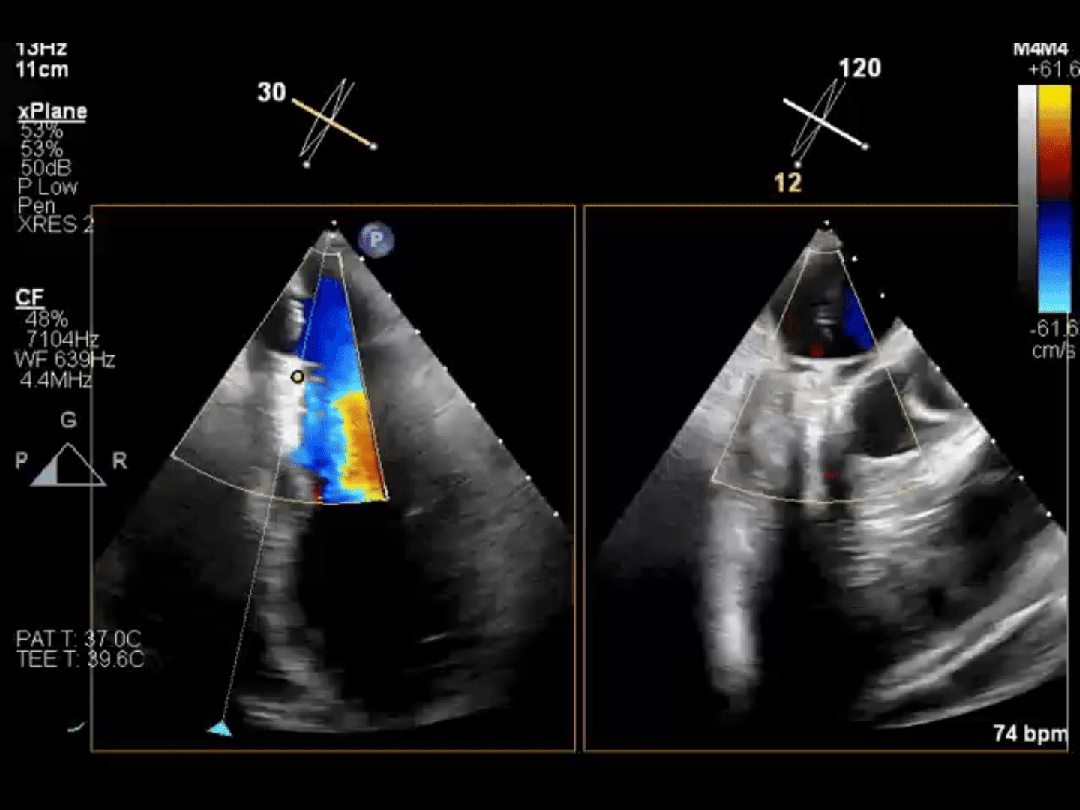

同样幸运的还有李爷爷。他因心脏二尖瓣脱垂导致血液严重反流,随时可能发生心衰。经过评估,医生为他选择了经导管二尖瓣钳夹术(TEER)。

手术中,医生通过大腿静脉送入特制夹子,在超声引导下精准夹合脱垂的瓣叶。整个手术不到 1 小时,李爷爷原本关不牢的「心门」变得「严严实实」,术后反流明显减少,充分彰显了团队的技术实力。